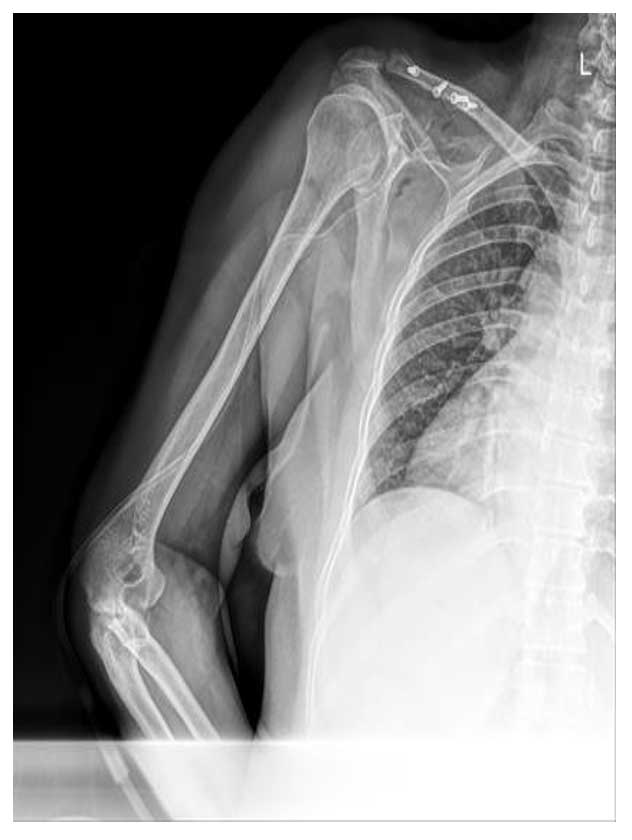

Genç erkek hasta, omuz ön bölümünde uzun süredir devam eden ağrı ve hareket kısıtlılığı şikayetleri ile başvurmuş; yapılan görüntüleme ve biyopsi sonucunda korokoid yerleşimli kondrosarkom tanısı doğrulanmıştır.

Ameliyat Öncesi: Röntgende korokoid üzerinde düzensizlik, tomografide genişleme, kortekste incelme ve kıkırdak dokusu, MR’da heterojen kitlenin boyutları görülmekte.

Ameliyat Sonrası: Röntgende korokoid eksizyonu yapıldığı, klavikulanın vidalar ile fikse edildiği görülmekte.